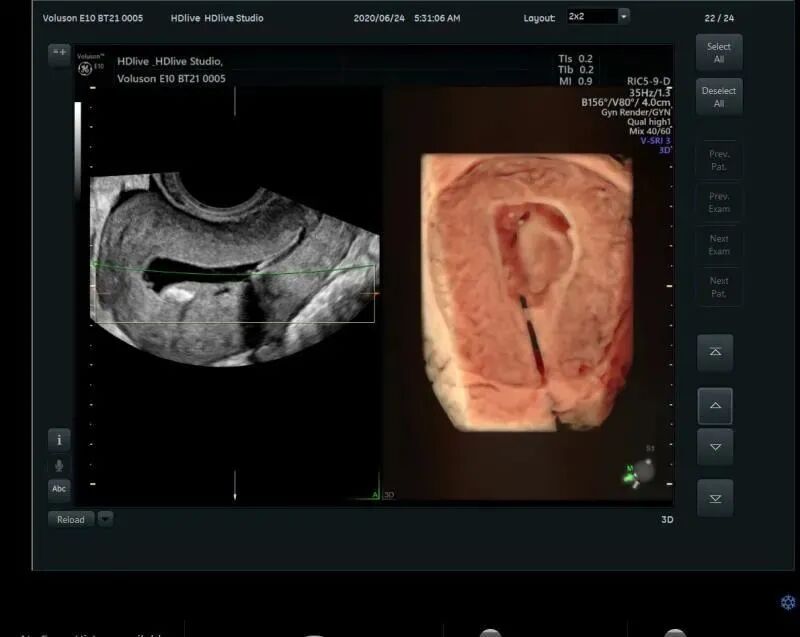

五、妇科疾病领域

更精准的图像能够对子宫畸形及宫腔病变、输卵管、卵巢、卵泡等进行全面评估;盆底三维四维超声有着多平面成像的优势,通过容积数据采集获得更清晰的图像,为临床诊断提供更丰富、有效的信息;妇科肿瘤方面,“煊流技术”提高了微小血管的敏感性有助于肿瘤良恶性的鉴别诊断。